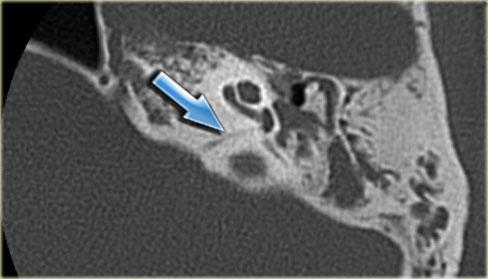

Bên trái là hình ảnh cắt ngang và cắt vành của một bệnh nhân nam 64 tuổi.

Hành tĩnh mạch cảnh nhô lên cao hơn bờ dưới của ống bán khuyên sau (mũi tên).